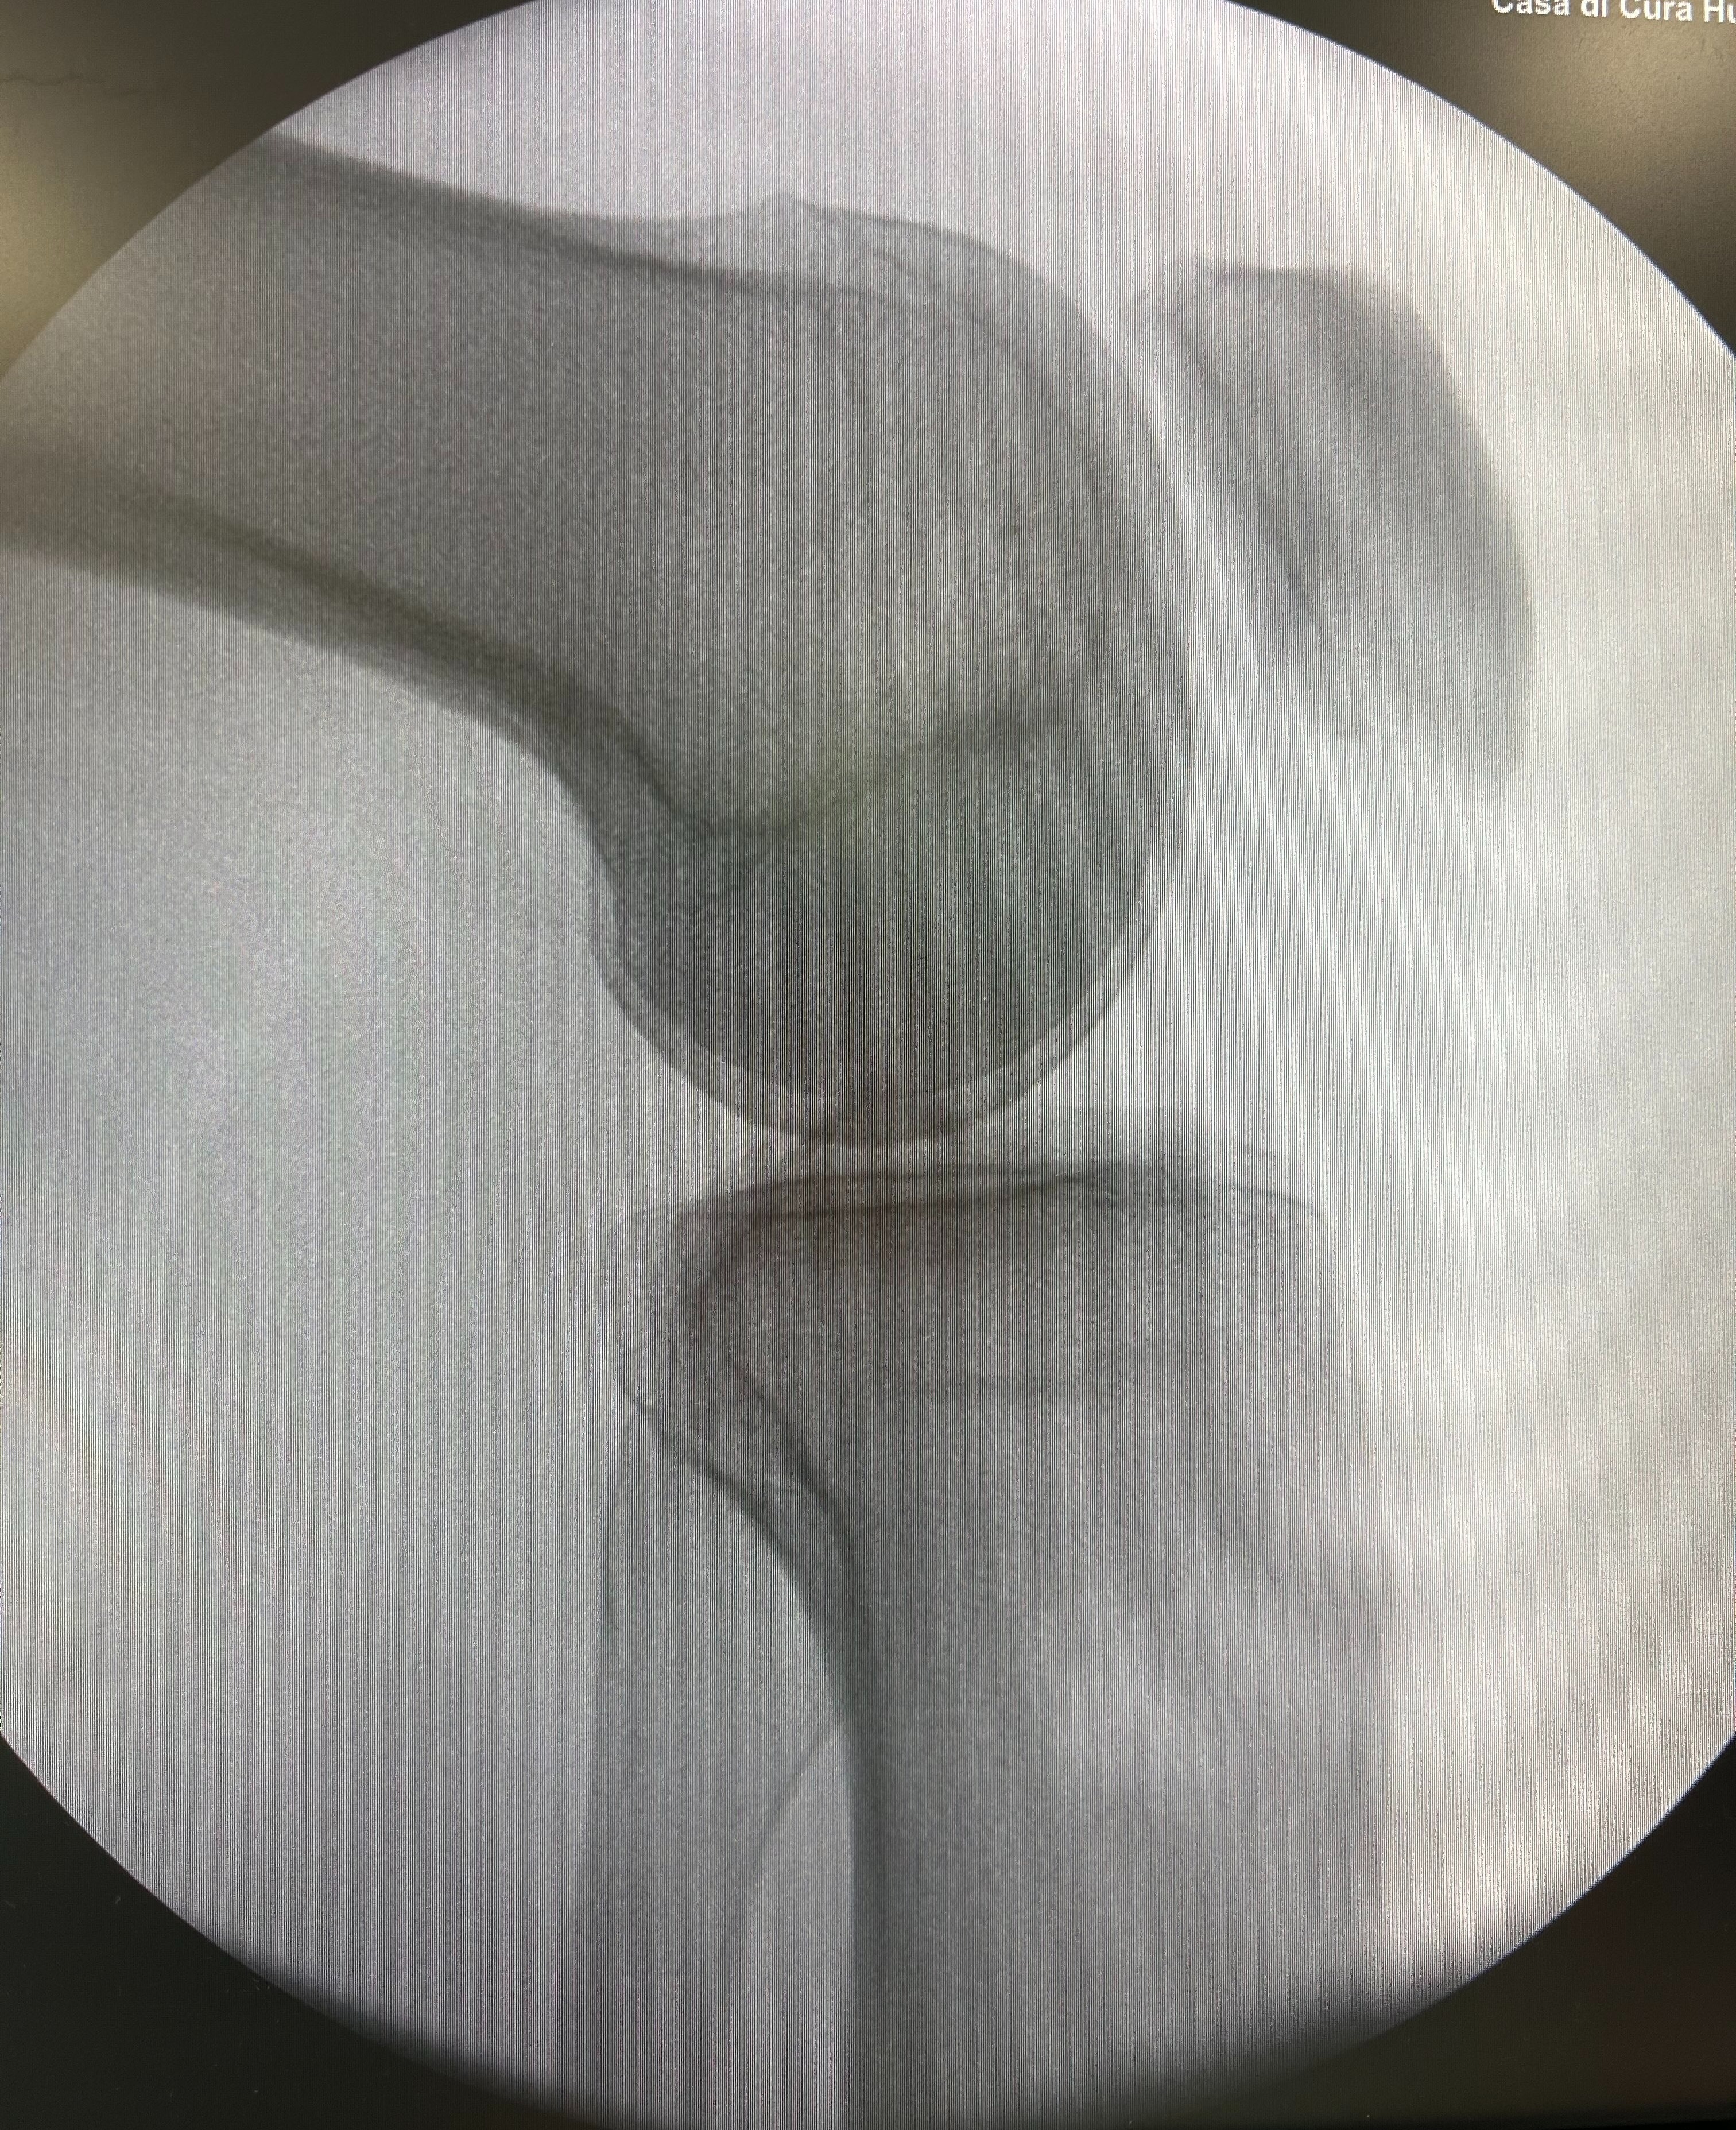

Tesi di Laurea dal titolo: “Ricostruzione del legamento crociato anteriore con tecnica anatomica (portale Anteromediale): Risultati oggettivi e soggettivi e ritorno allo sport”

2022-2023 Chirurgia del Ginocchio - CoGiTo - Cellini - Chirurgia del Ginocchio

OTTOBRE 2023 - Specializzazione in ortopedia e traumatologia con titolo: “Riparazione delle ramp lesion dai portali artroscopici anteriori con tecnica all-inside: risultati clinici e ritorno allo sport”